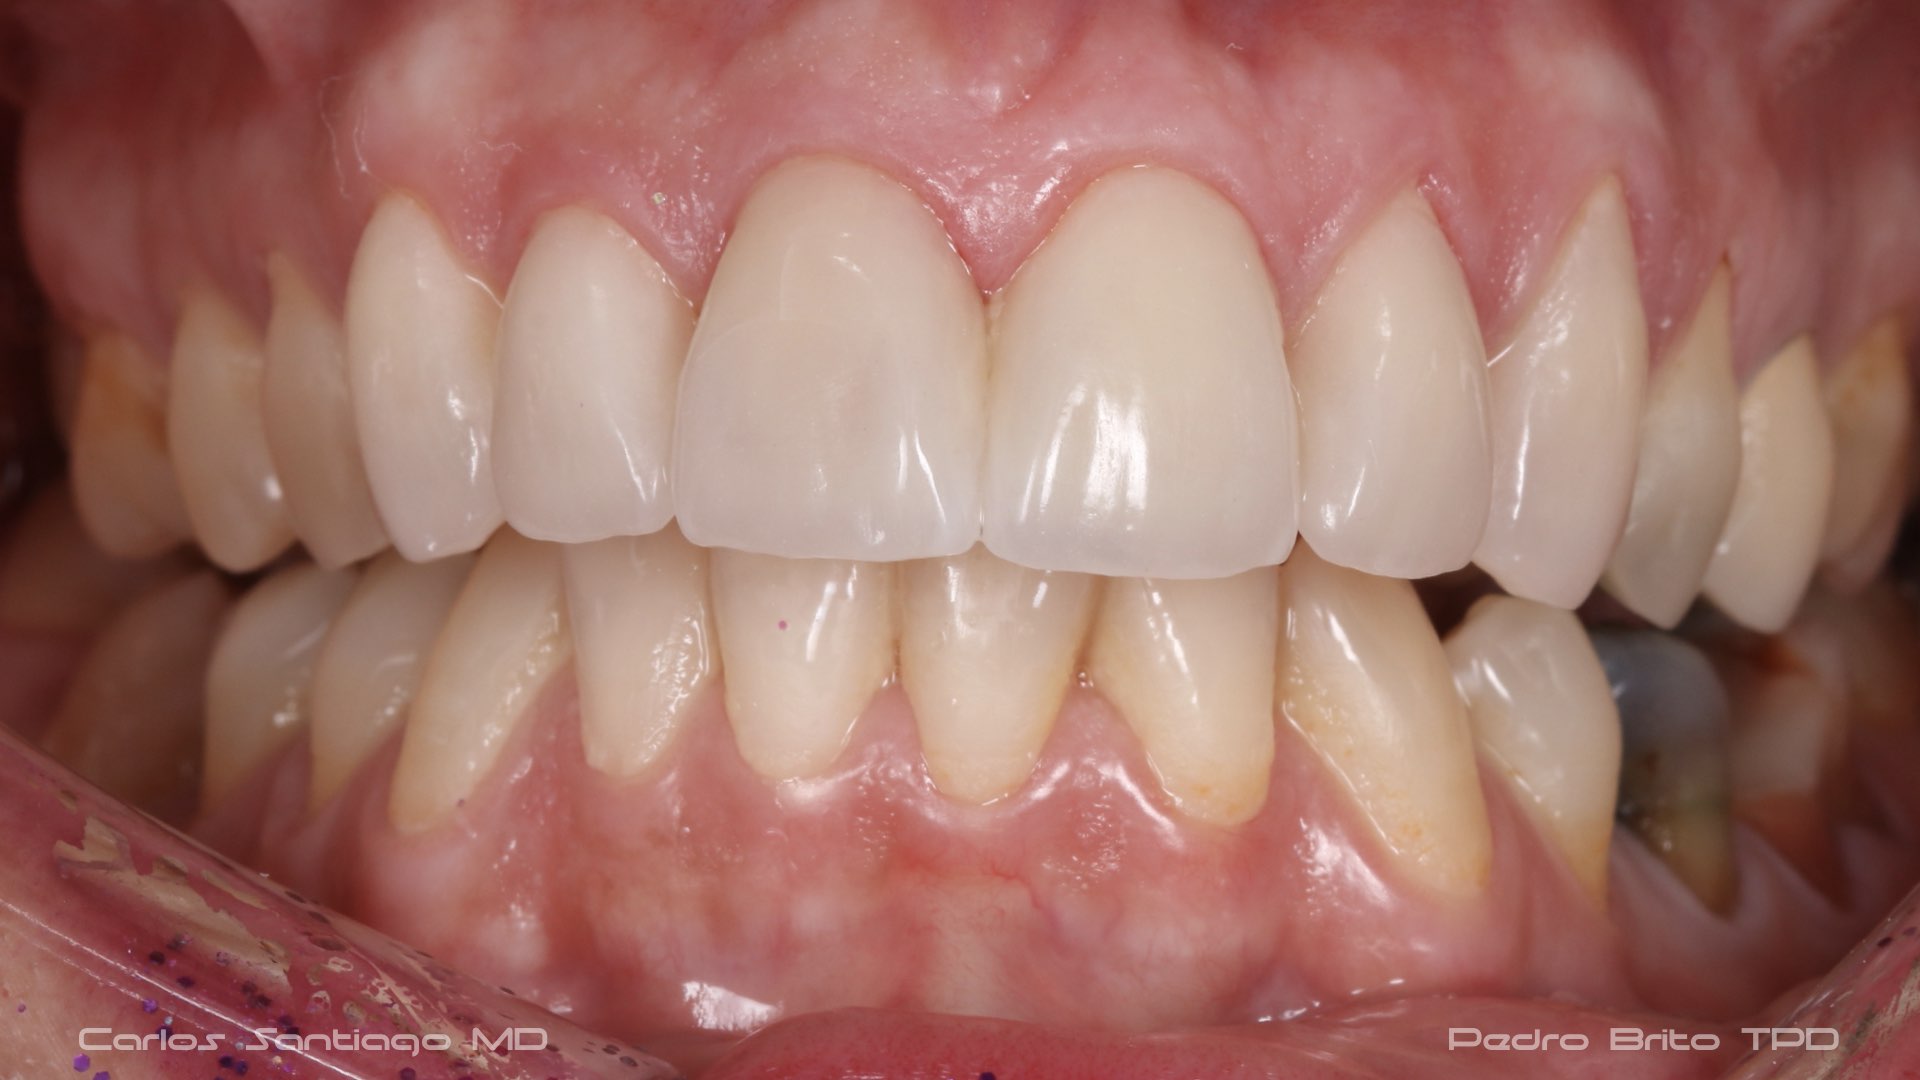

As Facetas Cerâmicas (lentes de contacto dentárias ou laminados), permitem corrigir da maneira mais estética e conservadora possível, problemas de forma e tamanho, côr e posição dos dentes, bem como substituir restaurações antigas e inestéticas.

São aderidas químicamente ao esmalte dentário de uma forma permanente, com o objectivo de melhorar a estética dos nossos pacientes.